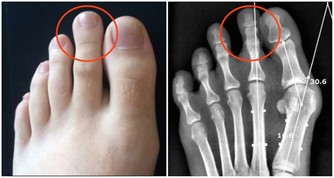

傷腎飲食習慣4:海鮮配啤酒

這種吃法曾被腎內科醫生稱為“最傷腎的吃法”。大量吃海鮮會產生過多的尿酸和尿素氮等代謝廢物,加重腎臟排泄負擔。而大量喝啤酒的話,腎臟發生疾病的機率會增高,也會讓尿酸堆積在腎小管裡面而出現堵塞情況,情況嚴重的人還容易造成腎臟衰竭。